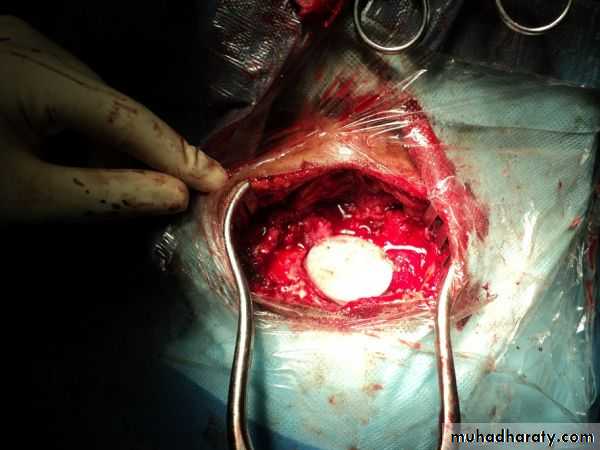

CEREBELLUM AFTER SURGERY FOR MB